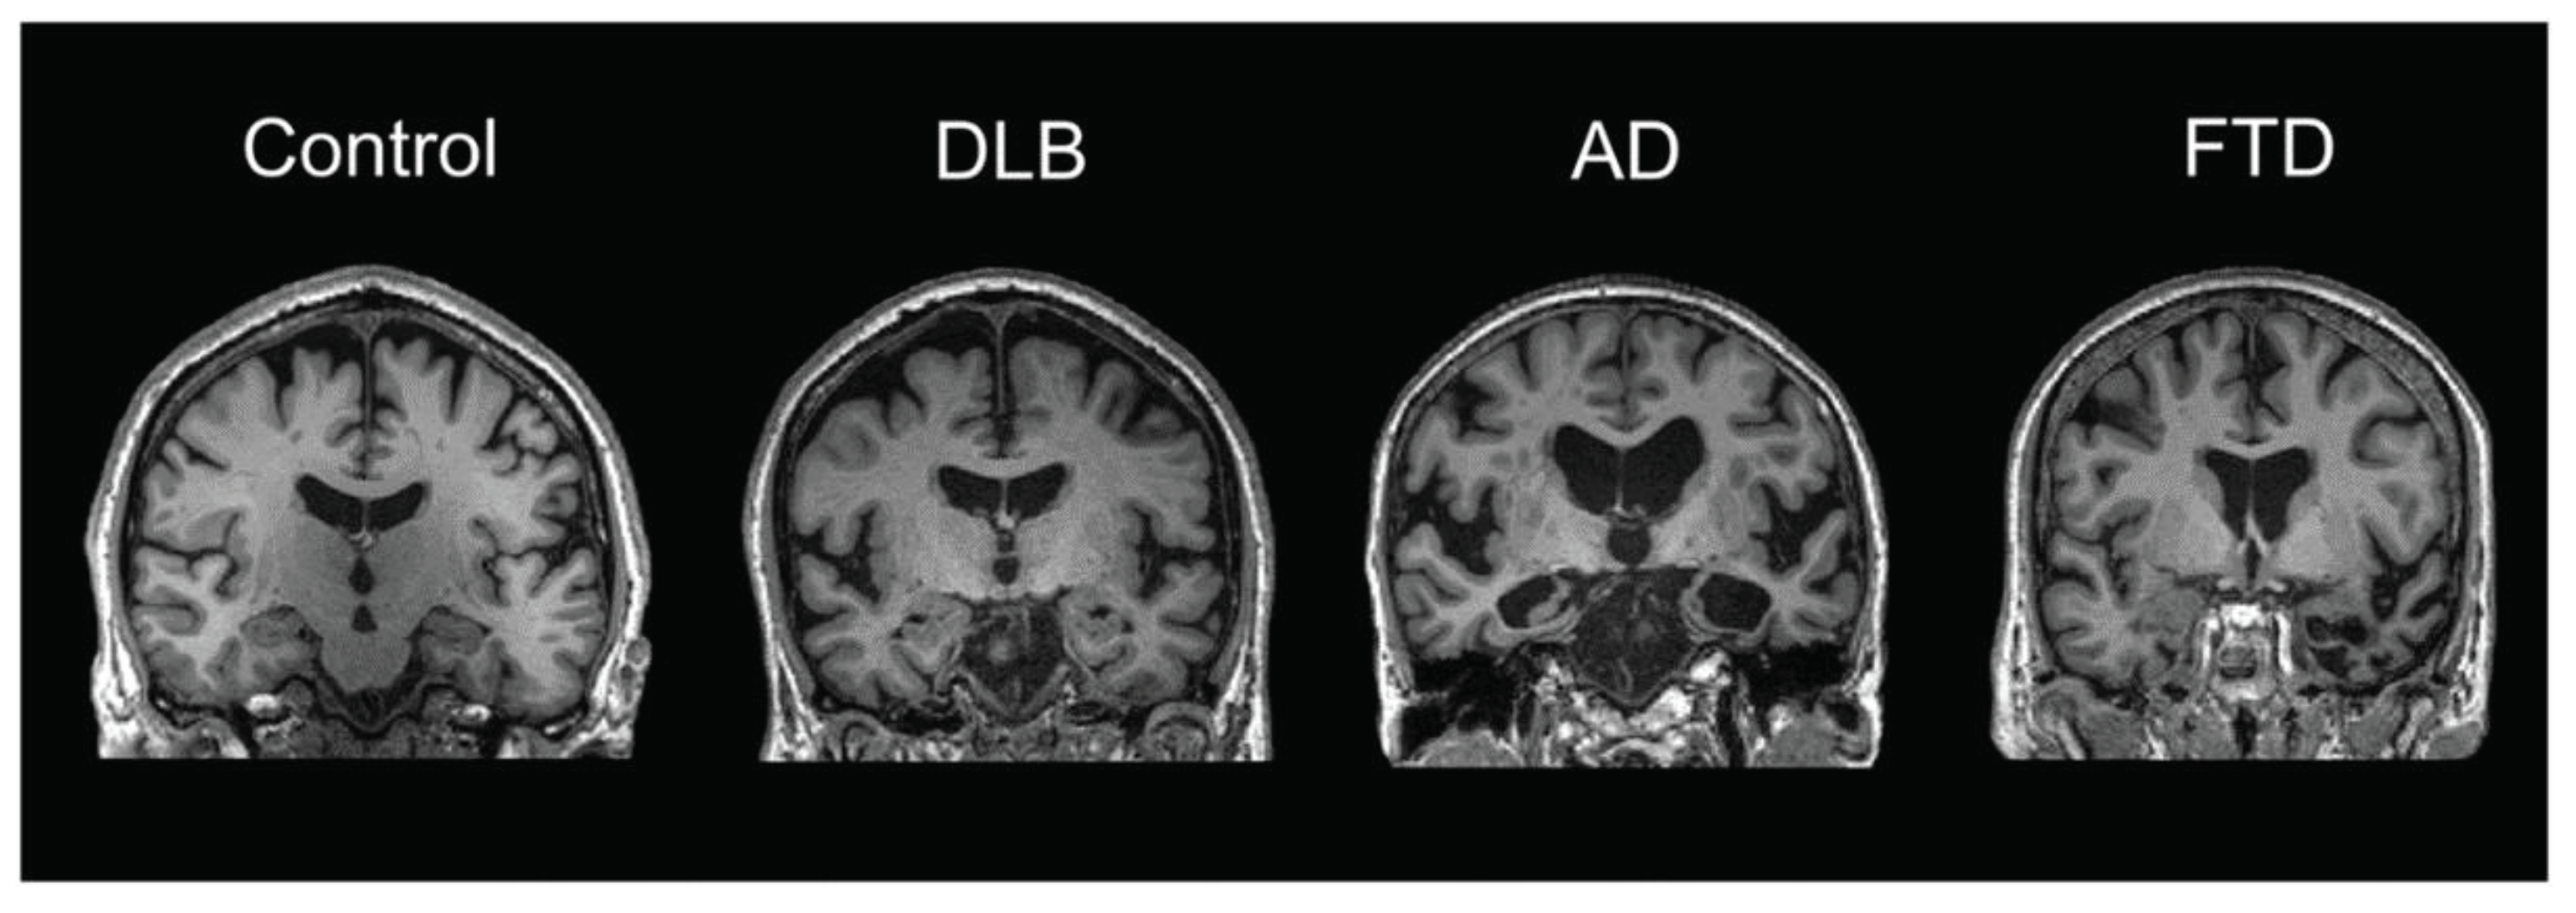

- Chouliaras, L.; O’brien, J.T. The use of neuroimaging techniques in the early and differential diagnosis of dementia. Mol. Psychiatry 2023, 28, 4084–4097. [Google Scholar] [CrossRef]